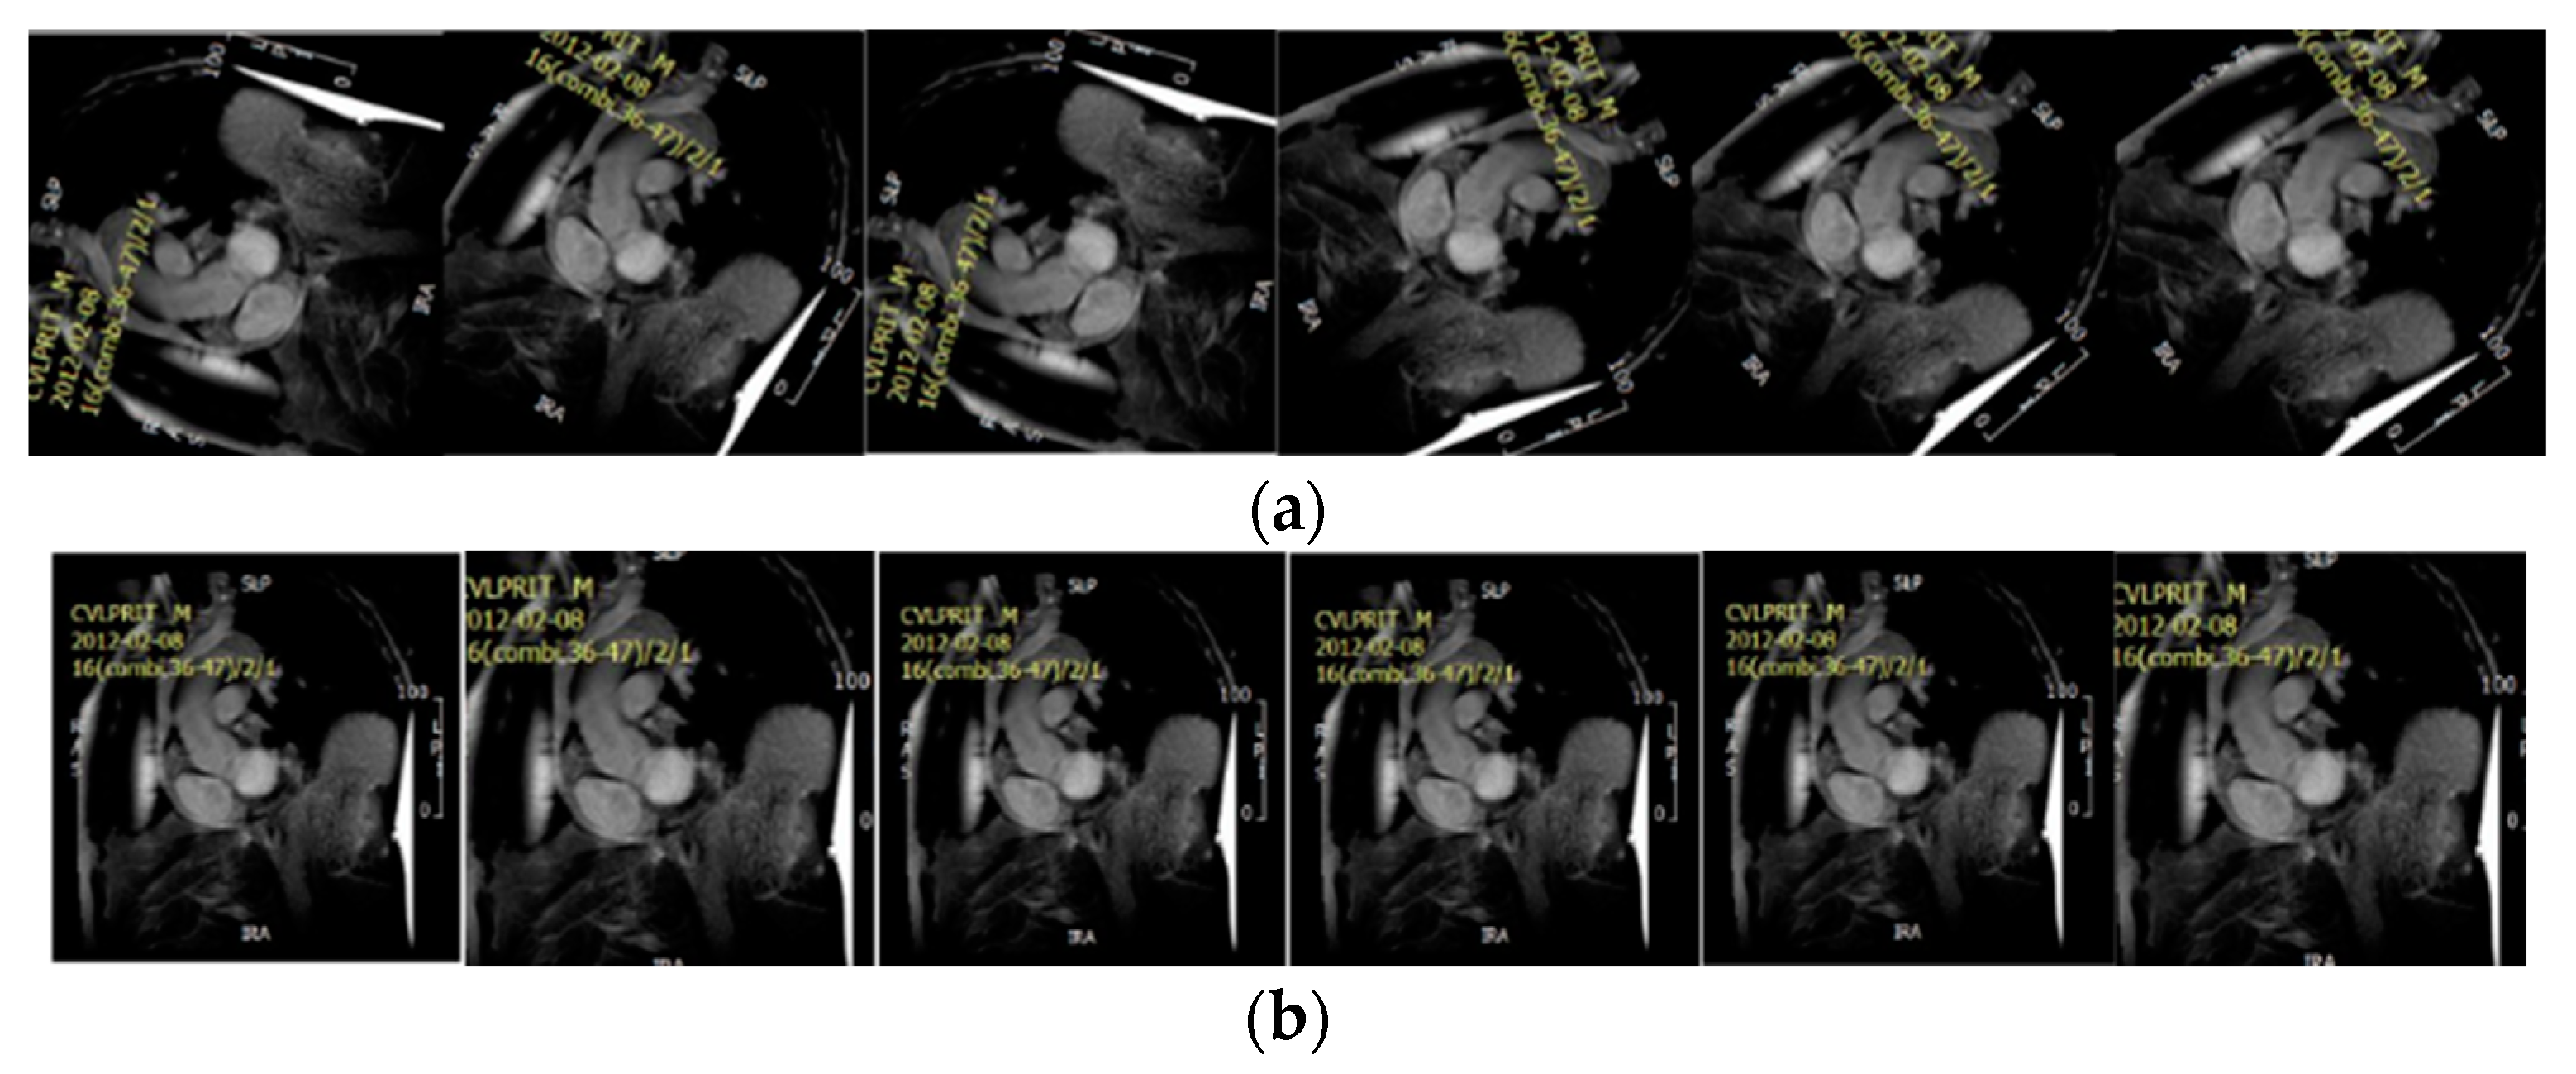

2. Materials

4.1. Data Preparation